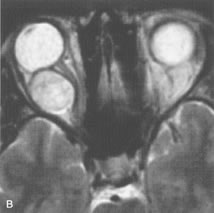

INTRAOCULAR TUMORS

On MRI, uveal melanomas have a typical appearance that helps to differentiate them from other primary and secondary intraocular tumors as well as choroidal detachments. Pigmented melanomas are hyperintense on Tl-weighted images, hypointense on T2-weighted studies, and hyperintense on proton density–weighted examinations (Fig. 24).30,31,50,80–82 These signal characteristics have been attributed to the paramagnetic properties of melanin because of stable free radicals that shorten the T1 and T2 relaxation times. Moderate enhancement is seen on postgadolinium T2-weighted images. Gadolinium-enhanced T1-weighted images are particularly sensitive in detecting choroidal melanomas.83 MRI may be less sensitive in detecting extrascleral extension of tumor than echography performed by an experienced ultrasonographer.84

Fig. 24. A. T1- and (B) T2-weighted MR scans demonstrate a small nodular intraocular mass (arrows) that is very hyperintense on the T1-weighted scan and hypointense on the T2-weighted image. This signal intensity pattern is due to the presence of free radicals within melanin granules. C and D. Postcontrast fat-suppressed T1-weighted scans demonstrate homogeneous intense enhancement of the lesion and no evidence of seleral penetration or optic nerve invasion.

Tumors metastatic to the choroid are hyperintense on T1- and T2-weighted images.24 The signal characteristics, however, may be similar to those seen with choroidal melanoma. Choroidal hemangiomas, on the other hand, have an intermediate signal on T1-weighted sequences and become hyperintense on T2-weighted images50 as well as proton density–weighted images.81

Retinoblastomas display moderate signal intensity on T1-weighted studies and a low signal on T2-weighted images.31,80,85 Calcification can be easily detected by CT and ocular ultrasonography but is not imaged by MRI.25,50 The presence of optic nerve involvement is best evaluated by MRI.